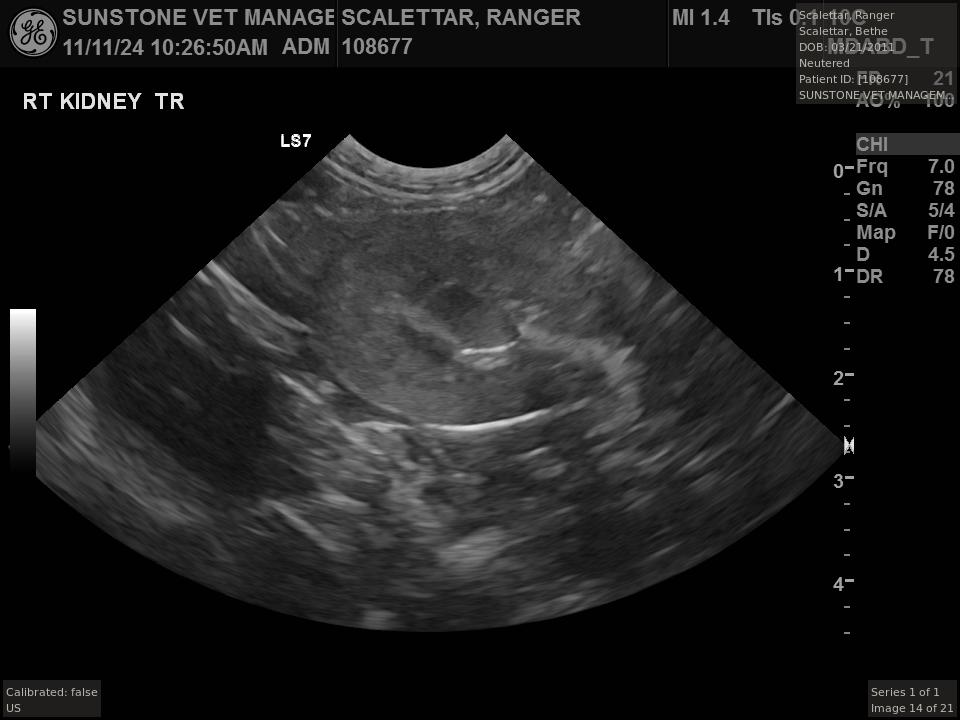

Veterinary ultrasound examinations of the thorax and/or abdomen typically include a number

of views selected to assess the health and function of internal organs. Unlike with radiography,

the images do not include the lungs because ultrasound reflects off the outer boundaries of the

lungs, making it difficult to see inner structures.

The veterinarian generated a series of images showing different organs and substructures by

changing the position and orientation of the ultrasound transducer. The images were collected

in a defined order, which is repeated from patient to patient, ensuring that nothing is missed. In

Ranger's case, the sonographer collected about twenty images during an examination that

lasted about fifteen minutes.

The sonographer stated that Ranger's ultrasound images were largely normal for an older cat. In particular, they show changes in the kidneys that are commonly noted in geriatric cats and that reflect a risk for the development of chronic kidney disease. However, the images did not show any significant abnormalities in Ranger's stomach, intestines, and associated lymph nodes. Nonetheless, the results did not rule out recurrence of Ranger's small cell lymphoma.